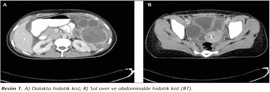

Kadın doğum polikliniğine iki gündür süren karın ağrısı şikayetiyle başvuran 19 yaşındaki kadın hastanın anamnezinde; evli olduğu, üç gebelik ve bir düşük geçirdiği, yaşayan iki çocuğunun olduğu tespit edilmiştir. Yapılan fizik muayenesinde; alt abdominal bölgede minimal hassasiyet mevcut olup, yapılan vajinal muayenesinde; servikal hassasiyet, lökore tespit edilmiş; kontrasepsiyon amaçlı dört yıldır kullandığı rahim içi aracın (RİA) olduğu görülmüştür. Hastanın vücut sıcaklığı 38.1°C, kan basıncı 110/70 mmHg ve nabzı 87/dakika olup, laboratuvar sonuçlarına göre beyaz küre: 4600/µl, hemoglobin: 10 g/dl, AST: 23 U/L, ALT: 22 U/L, LDH: 173 U/L ve C-reaktif protein: 6.02 mg/L'dir. İlk muayene bulguları dikkate alınarak; tuboovaryan apse ön tanısıyla takip ve tedavi için yatışı yapılan hastanın transabdominal ultrasonografi (US)'sinde, uterin kavitede RİA, douglasta mayii, sol overde 44 x 43 mm ince duvarlı, septalı ve dalakta 65 x 65 mm ince duvarlı multiloküle kist görülmüştür. Bilinen kist hidatik öyküsü olmayan hastada US bulguları sonrası kontrastlı abdominal bilgisayarlı tomografi (BT) yapılmış ve dalak, ön abdominal duvar ve sol overde multiveziküllü kistik kitleler görülmüştür (Resim 1). Ateşi yükselen ve vital bulguları kötüleşen, karın ağrısı artan hasta acil laparoskopiye alınmış, eksplorasyonda; abdominal kavitede 1000 cc serbest pürülan mayi, ön abdominal duvara yapışık 40 x 40 mm kistik kitle, tüm batında yaygın çok sayıda en büyüğü 30 x 30 mm'lik kistik kitleler ve ayrıca sol overde en büyüğü 40 x 30 mm olan, birkaç adet ince duvarlı loküle kistler tespit edilmiştir. Bu doğrultuda laparoskopik olarak sol ovaryan kistektomi uygulanmış ve kist perfore edilmeden çıkarılmıştır. Batın, batın ön duvarı ve dalaktaki kistler nedeniyle genel cerrahi uzmanı operasyona dahil olmuş; göbek altı medyan insizyonla laparotomiye geçilmiş, abdominal kistektomi ve splenektomi uygulanmış ve batın yaklaşık 3000 cc serum fizyolojikle yıkanmıştır. Yapılan makroskobik incelemede hidatik kist için patognomonik olan germinatif membran ve hidatik kum gözlenmiştir. Hastanın acilen ameliyata alınması nedeniyle operasyon öncesi indirekt hemaglütinasyon (IHA) testi yapılamamıştır. Postoperatif takip için hasta genel cerrahi servisine sevk edilmiştir.

Resim 1